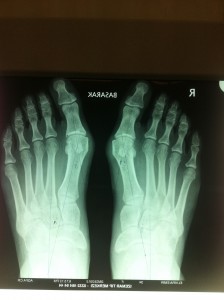

Olgu örneği: